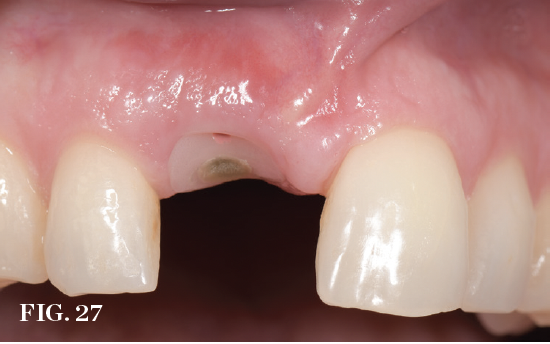

Immediate Tissue Guidance

In the immediate placement approach, implants should be planned and introduced using methods that create the possibility of placing a provisional restoration at the time of surgery to support the existing tissue contours. Although the restoration protocol is planned before treatment, the final decision of whether or not to follow through with it is based on the implant insertion torque/primary stability achieved as judged by the surgical clinician. Various techniques have been described that range from full-contour provisional crowns to partial guidance customized healing abutments with or without an overlying restoration. Delivering one of these transitional solutions can provide a barrier to retain any bone graft while potentially supporting the soft-tissue anatomy. In one 12-month randomized controlled trial, 3D ridge changes as expressed by soft-tissue resorption occurred following immediate placement; however, volume preservation was better when immediate provisionalization was carried out.36 Prosthetic guidance with custom healing abutments is recognized as an option to support the marginal tissue.37 Appropriate design is essential to have a positive impact on tissue anatomy support and outcomes (Figure 25 through Figure 27).

(27.) View of an immediate implant site 2-weeks postoperatively. Note the ideal design of the custom healing abutment supporting and guiding the marginal gingiva.

Figure 27